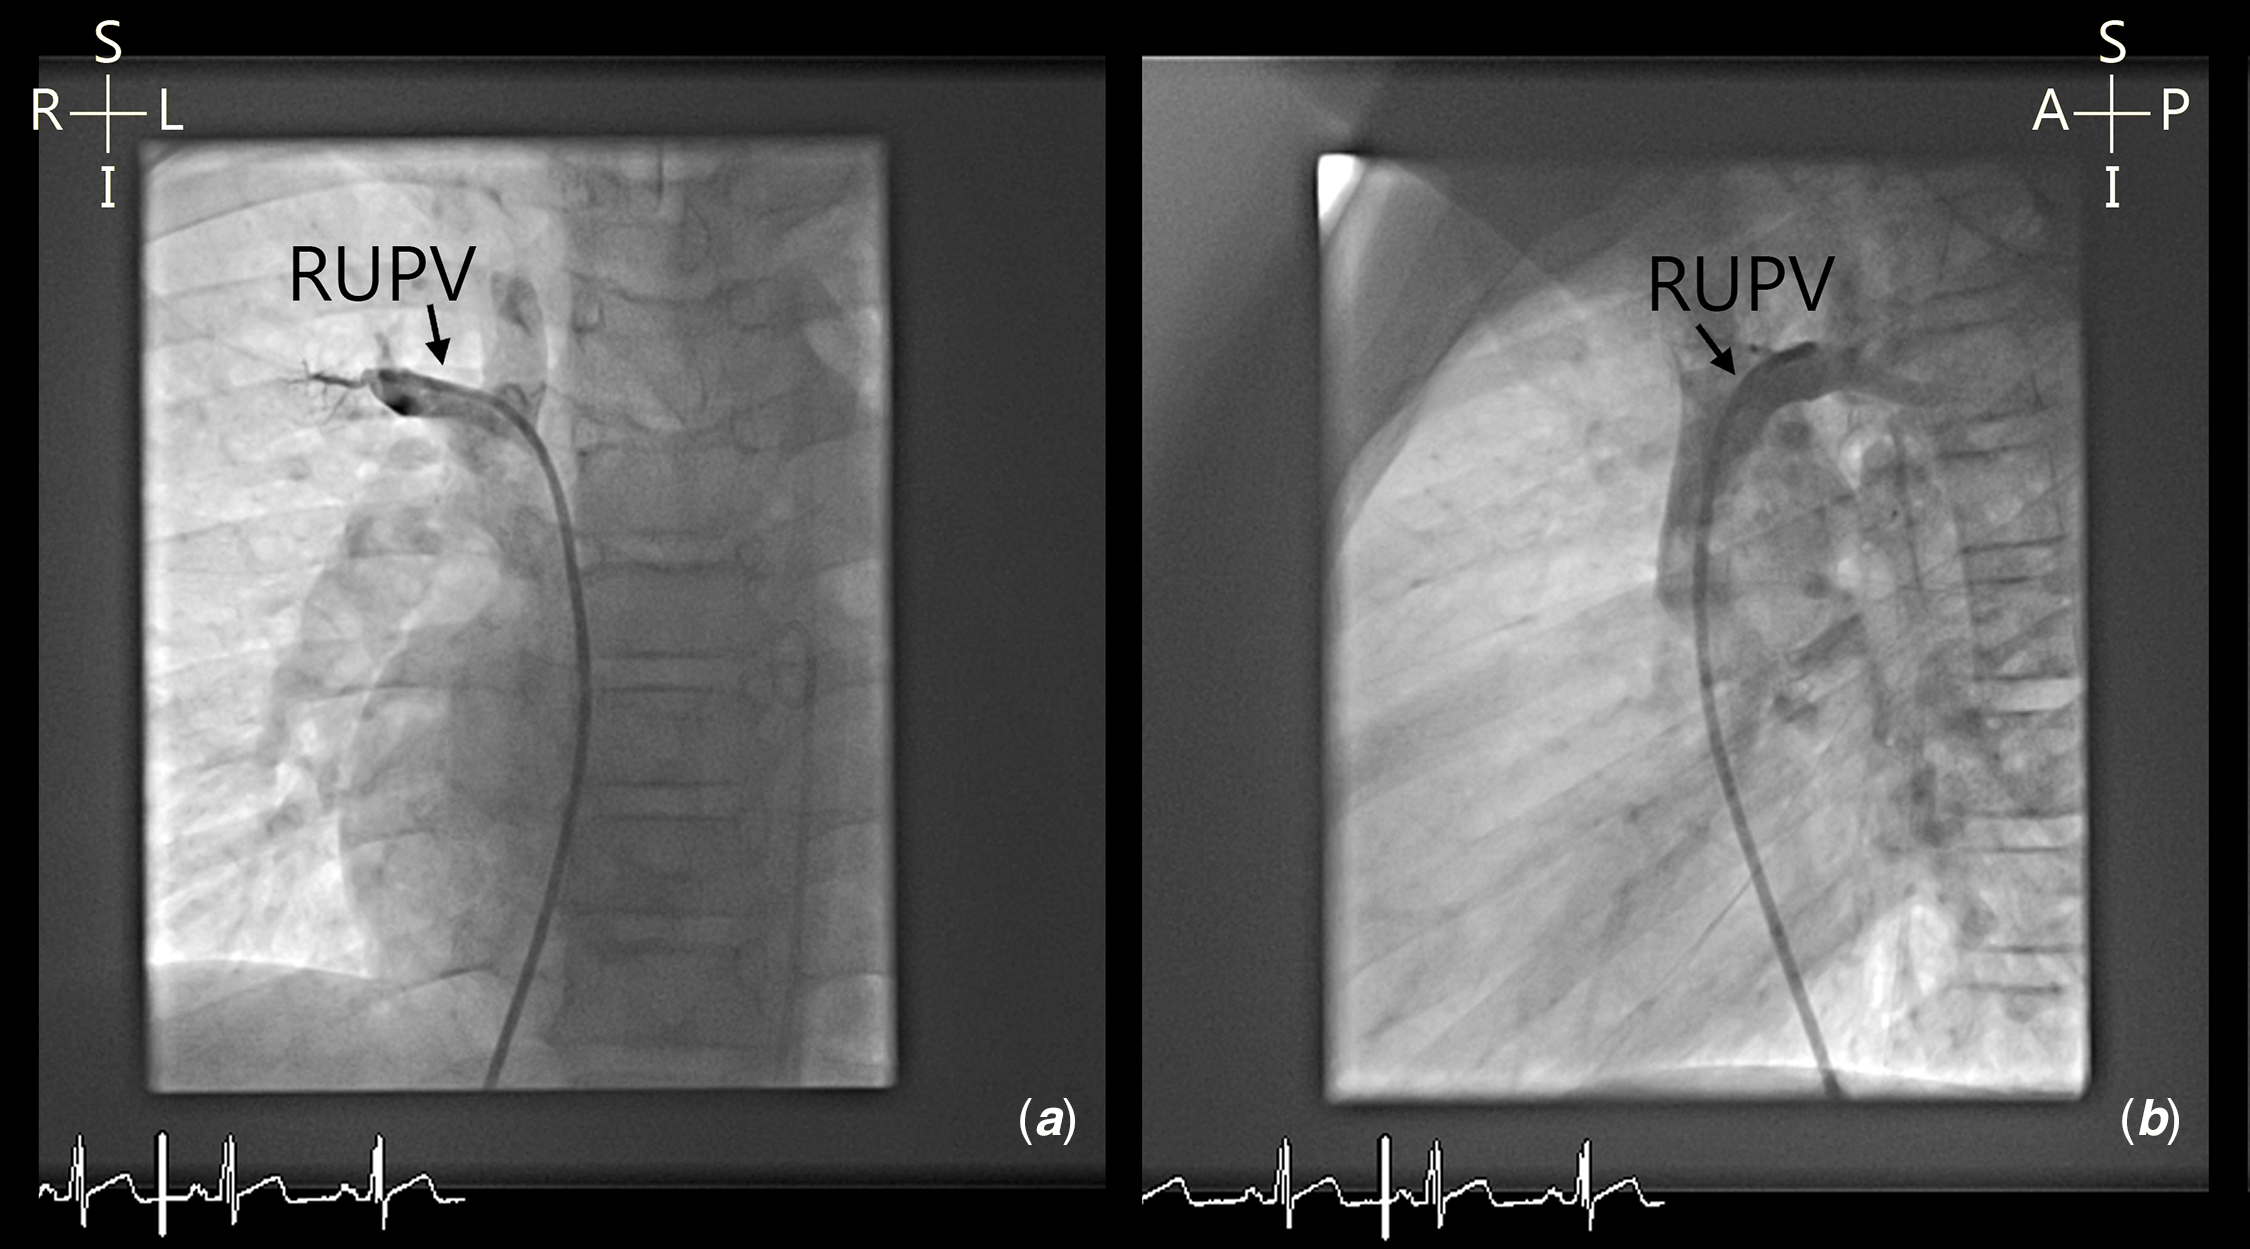

Five patients had complex pulmonary venous variants. Four patients had high insertion of anomalous vein into the superior caval vein (Fig 4) and three patients had multiple anomalous veins draining to different sites, two of whom had high drainage of one vein to the superior caval vein (Fig 5). Six of the 37 patients have bilateral superior caval veins.

Figure 5. ( a and b ) Cardiac angiography demonstrating high insertion of right upper pulmonary vein (RUPV) into right superior caval vein.